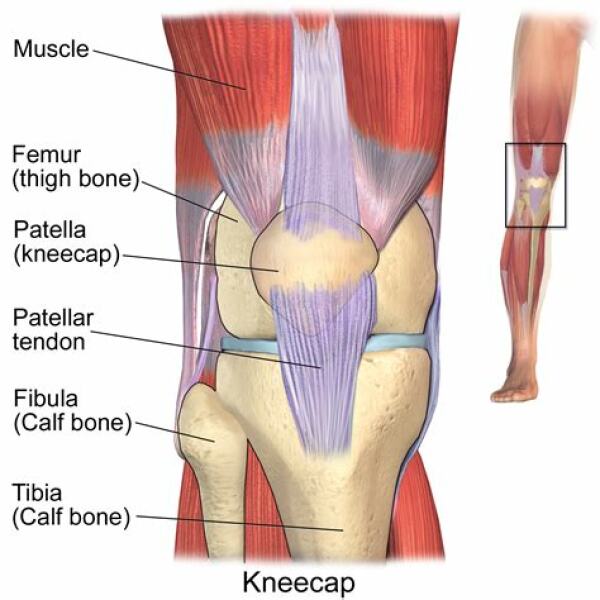

OP says the side of the knees though. Osgood Schlatter’s affects the patellar tendon (see pic above) so is in the middle.

lumps at the side of the knee are not indicative of Osgood Schlatters, which affects the patellar tendon.